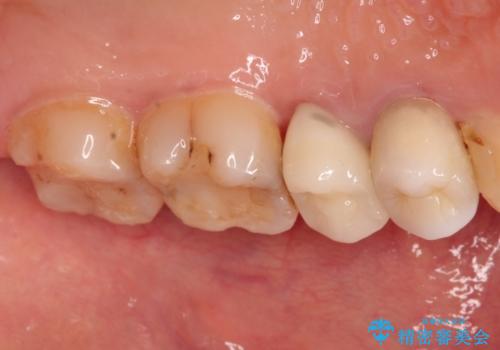

かぶせ物と詰めてある修復物を除去すると歯肉の中まで虫歯になっていました。

歯を部分矯正で引き上げて、虫歯を徹底的に取り除き、適合の良いかぶせ物を装着する計画としました。

深い虫歯の治療は、治療が長期化したり、困難になることがあります。

虫歯にならないことも大事ですが、治療した歯の再治療が必要ないように、精密な治療をすることもとても重要です。